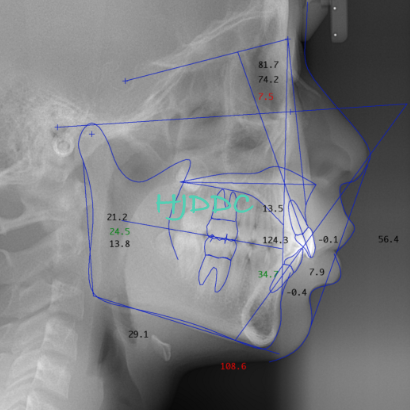

4)レントゲンの撮影2

一般的に『セファロ』と言われる頭部X線規格写真を撮影します。専用の分析ソフトを用いることで、患者さまのお顔の特徴を数値化し、治療方針決定の参考にします。お子様の成長記録(成長観察)に用いることも可能です。詳細はカウンセリング時にお尋ねください。